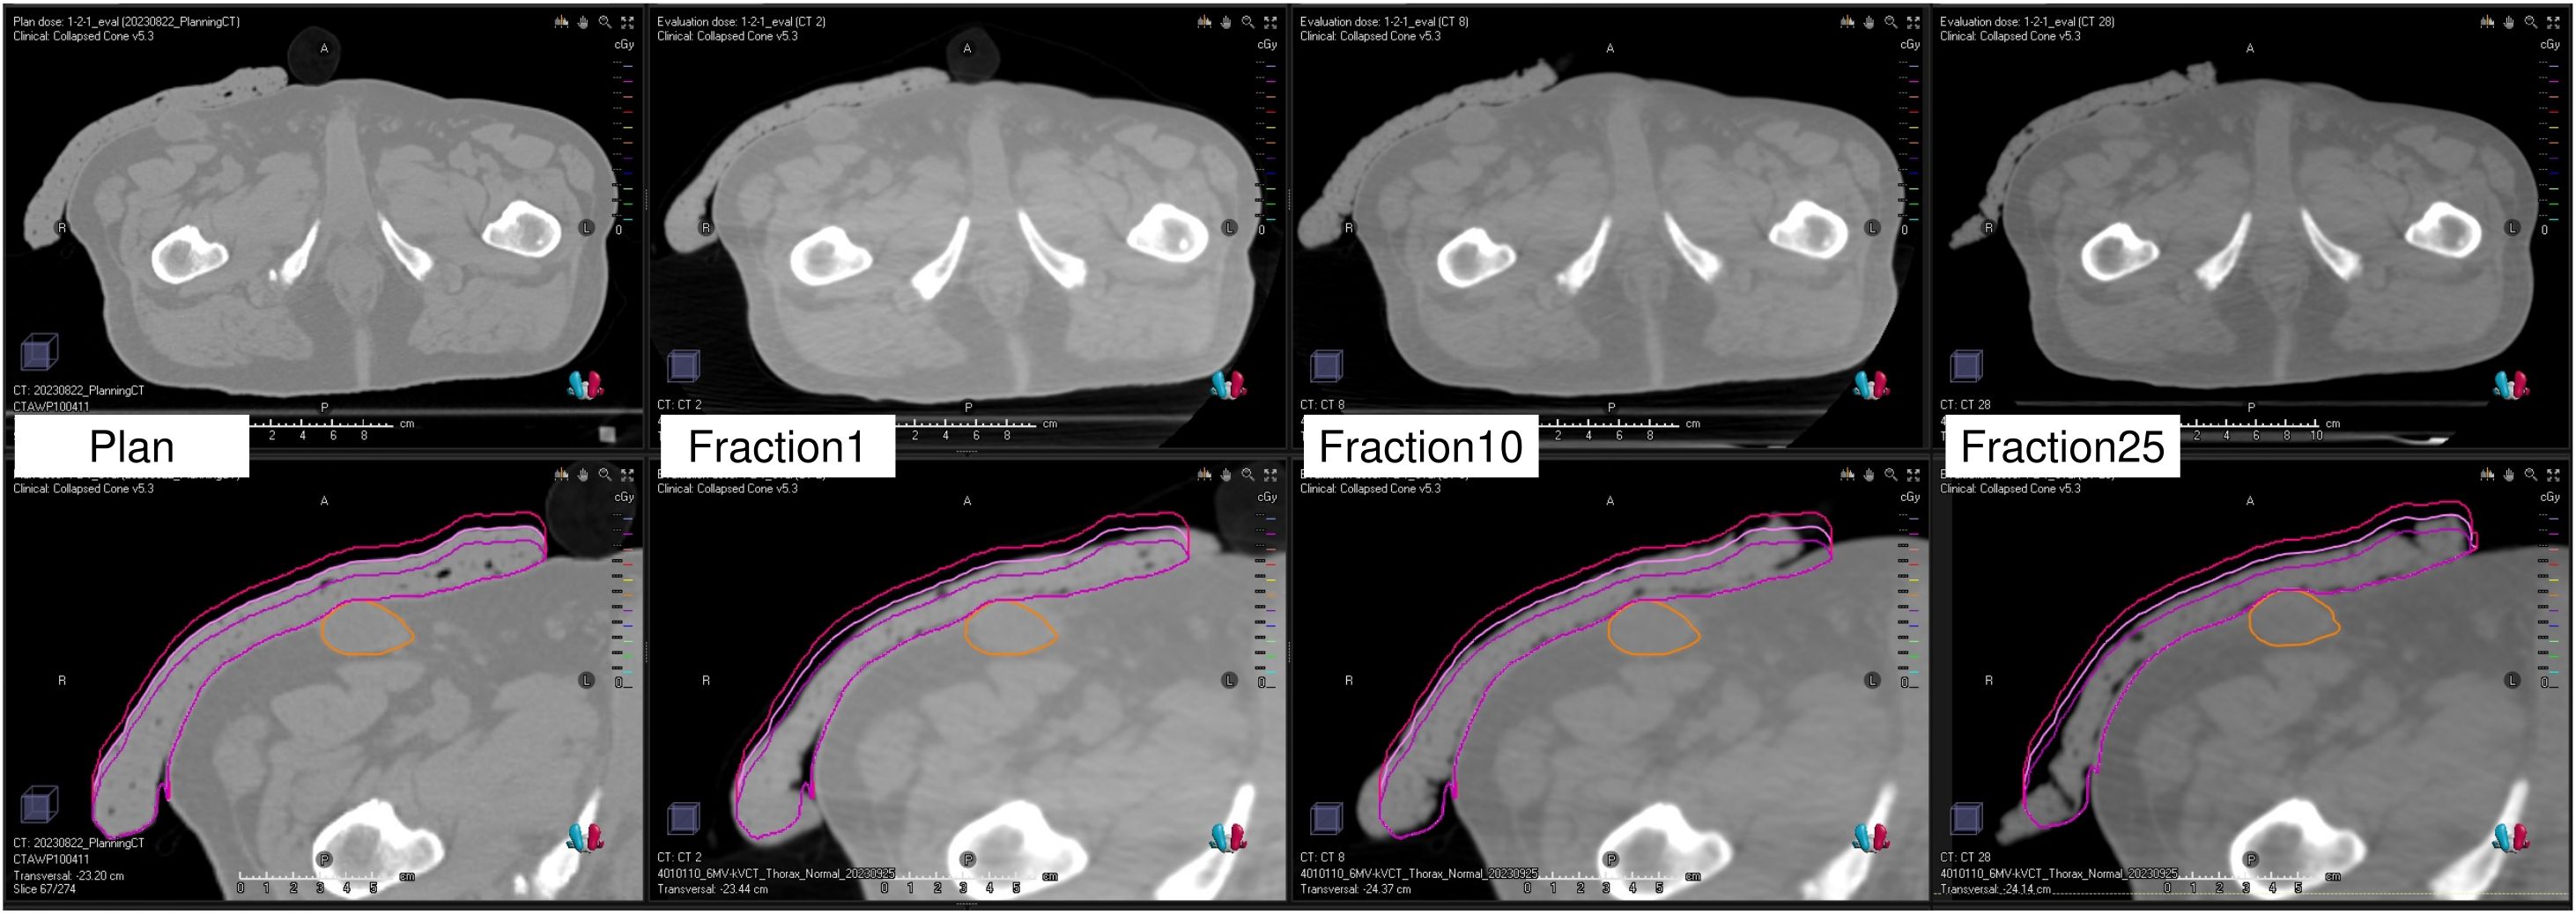

Background: Flat commercial boluses for superficial tumor radiation therapy often fail to conform to irregular body surfaces, resulting in air gaps that reduce dose coverage and uniformity. Although three-dimensional printed custom boluses have been developed to address this issue, the plastic material rigidity and time-consuming fabrication process limit their application. This study aimed to evaluate a flexible and easily moldable Super Stuff bolus as a practical alternative. Methods: We conducted a three-part study using Radixact with the kilovoltage computed tomography (kVCT) system. First, surface dose measurements were performed using radiochromic film on a solid water phantom. Super Stuff boluses of varying thicknesses (up to 20 mm) were compared with commercial boluses. Second, long-term stability was assessed over 65 days for dose delivery, thickness (via CT-based measurements), and CT number. Finally, in a clinical case of Ewing's sarcoma, setup reproducibility and conformity were assessed using Radixact's kVCT imaging. Delivered dose distributions were compared with the planned distribution using dose–volume histogram parameters and gamma analysis. Results: Surface dose measurements demonstrated that the maximum variation in surface dose among Super Stuff boluses with thicknesses ranging from 10.7 to 19.8 mm was within 4%. Over 65 days, the Super Stuff bolus showed good long-term stability. Changes in thickness were limited to a maximum of 1.6 mm, and fluctuations in CT number remained stable at 17.9 ± 1.2 Hounsfield units. In the clinical setting, kVCT imaging provided clear visualization of the Super Stuff bolus, and setup reproducibility was maintained throughout the treatment course. Air gaps were also minimized. Furthermore, gamma analysis (3%/2 mm) confirmed high dosimetric reproducibility throughout the treatment course, with passing rates exceeding 96% between the first and subsequent treatment fractions. Conclusions: The Super Stuff bolus provides notable clinical advantages for treating superficial tumors using Radixact with the kVCT system: consistent surface dose buildup, easy fabrication, and robust long-term physical and dosimetric stability. The seamless integration with the kVCT system enhances setup reproducibility, contributing to reliable and accurate dose delivery throughout the treatment course.